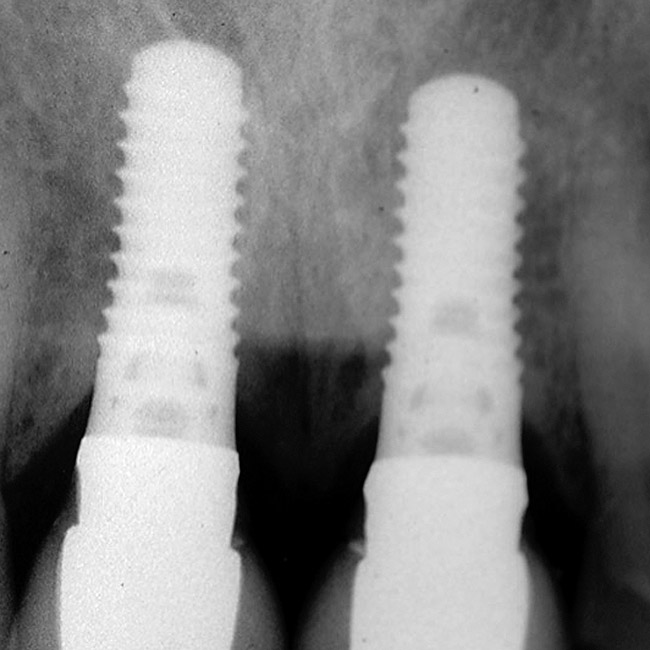

Figure 10  In these adjacent implants placed in the central and lateral positions, note the excellent interproximal bone but minimal interimplant distance.

Figure 10

1. It is difficult to place adjacent implants in a central and lateral position, or a lateral and cuspid position, and have 3 mm between the platform of the implants. This leaves a high risk of losing the interproximal crest of bone between the implants over time, with subsequent loss of papillary height (Figure 10, Figure 11, Figure 12 and Figure 13).